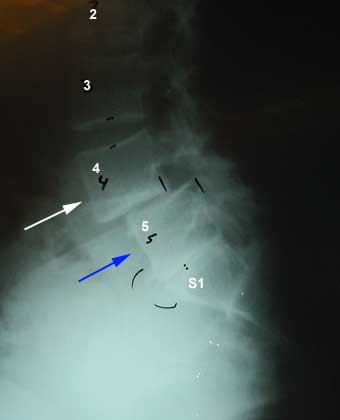

You can upload your MRI/Xrays for us to review;

We have partnered with mymedicalimages to offer a fast and secure way for patients to upload medical images for review by our medical team (“Practitioners”) . To get started, simply click on upload below.

*Our Practitioners’ MRI review is an informational review of the MRI images and/or report that you provide to us. This is not a form of diagnosis, treatment, correction, prevention or medical care. As such, the Practitioner’s MRI review should not be used as a determinant factor in any person’s physical or other health care, health treatment or health maintenance. No information provided by or through the Practitioner’s MRI review should ever be considered a substitute for any professional health care services, and you should consult with one or more appropriately licensed, registered and certified physicians, surgeons or other health care professionals for the same. In arranging for a Practitioner to provide an MRI review, neither K Hannani MD Inc® nor that Practitioner assumes any responsibility whatsoever, nor shall K Hannani MD Inc® or such Practitioner in any event or under any circumstances be liable in relation to your decision concerning your health care, health treatment or health maintenance, including without limitation any actions that you choose to take as a result of the Practitioner’s MRI review. A diagnosis and a final determination of whether you may benefit from treatment at K Hannani MD Inc® can only be made after you have been physically examined in person by one of our Practitioners.